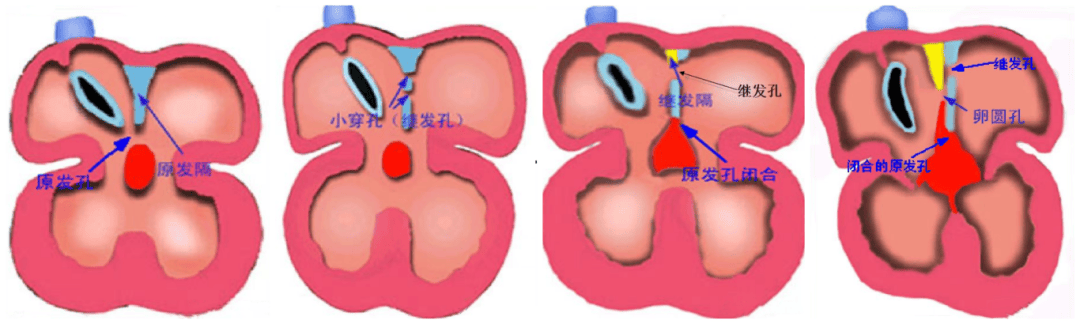

房间隔缺损(Atrial Septal Defect, ASD)是较常见的一种先天性心脏病,由于胚胎期房间隔发育、吸收或融合异常,导致左右心房之间残留未闭的房间孔。房间隔缺损可单独存在,或与其他心血管畸形合并存在。

房间隔缺损是由原发隔和继发隔组成,原发隔位于左侧,继发隔位于右侧。

房间隔缺损分原发孔型与继发孔型,通常房缺是指继发孔型。根据缺损部位不同分为四型:

中央型又称卵圆窝型:位于房间隔中部相当于卵圆窝部位,此型最常见,76%;

下腔型:缺损位于房间隔后下方,与下腔静脉入口相延续,12%;

上腔型:位于房间隔后上方,缺损与上腔静脉入口无明确界限,3.5%;

混合型:兼有上述两种以上的巨大房间隔缺损,8.5%。